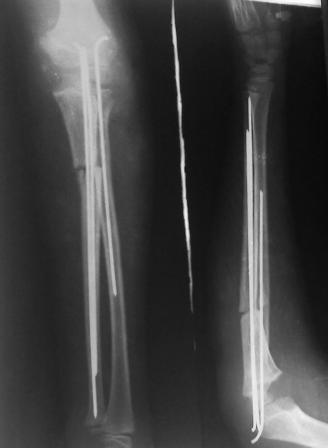

Иллюстрация к лечению застарелого повреждения Монтеджиа

Пациентка клиники детской травматологии ЦИТО

Многоуважаемые коллеги, всем большое спасибо!!! Да, здесь было повреждение Монтеджиа, когда нарисовал скиаграмму все стало понятно. Мне очень понравились рекомендации Константина Требухина, только немножко видоизменил; я считал так, если деформацию исправить то локт/кость должна удлиниться, и во вторых, если на аппарате низвести лучевую кость, то может наступить позиционное несоответствие в дистальном радиоульнарном сочленении. 28.02.08г операция - шарнирная остеотомия локтевой кости на уровне деформации, далее вскрыт плечелучевой сустав, удалены рубцовые тканы, после исправления варусной деформации и создания физиологического изгиба локтевой кости головка луча легко вправился, из части рубцовой ткани сделана пластика кольцевндной связки, трансартикулярная фиксация спицей, локтевая кость двумя спицами.

оперировали подобный случай около 6 мес назад. Отличие только в одном- давность травмы была до 2х лет. Использовали методику описанную в "Pediatric fractures and dislocations" Lutz von Laer, M.D.

Артротомия, иссечение рубцов, остатков кольцевидной связки. На проксимальный отдел локтевой кости стержневой аппарат (рекомендуют

Compact II выпущеный Stryker Howmedica, но за неименеем...), остеотомия проксимального отдела локтевой кости, вправление головки лучевой кости, замыкание аппарата, проверка стабильности головки

лучевой кости в движении, ушивание без пластики кольцевидной связки.